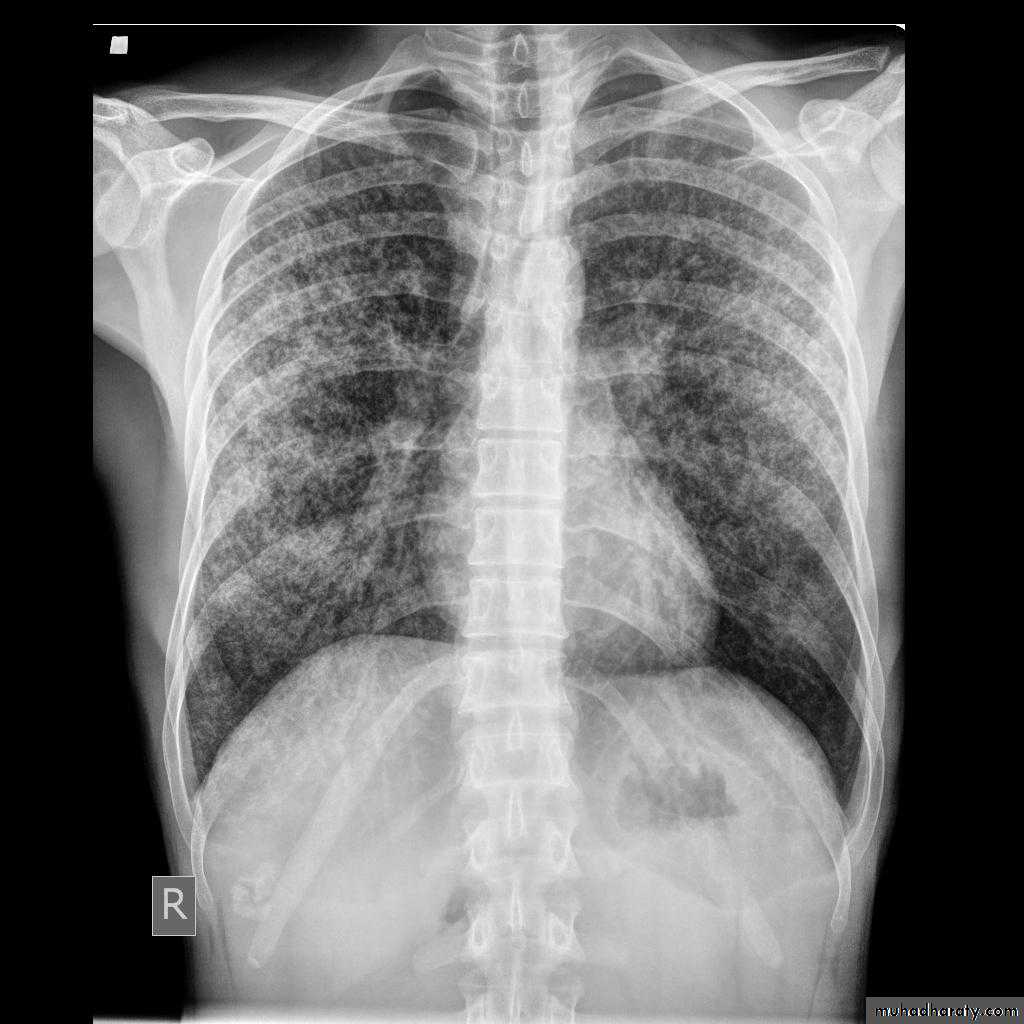

Miliary TB

65.Miliary TB

66.miliary TB